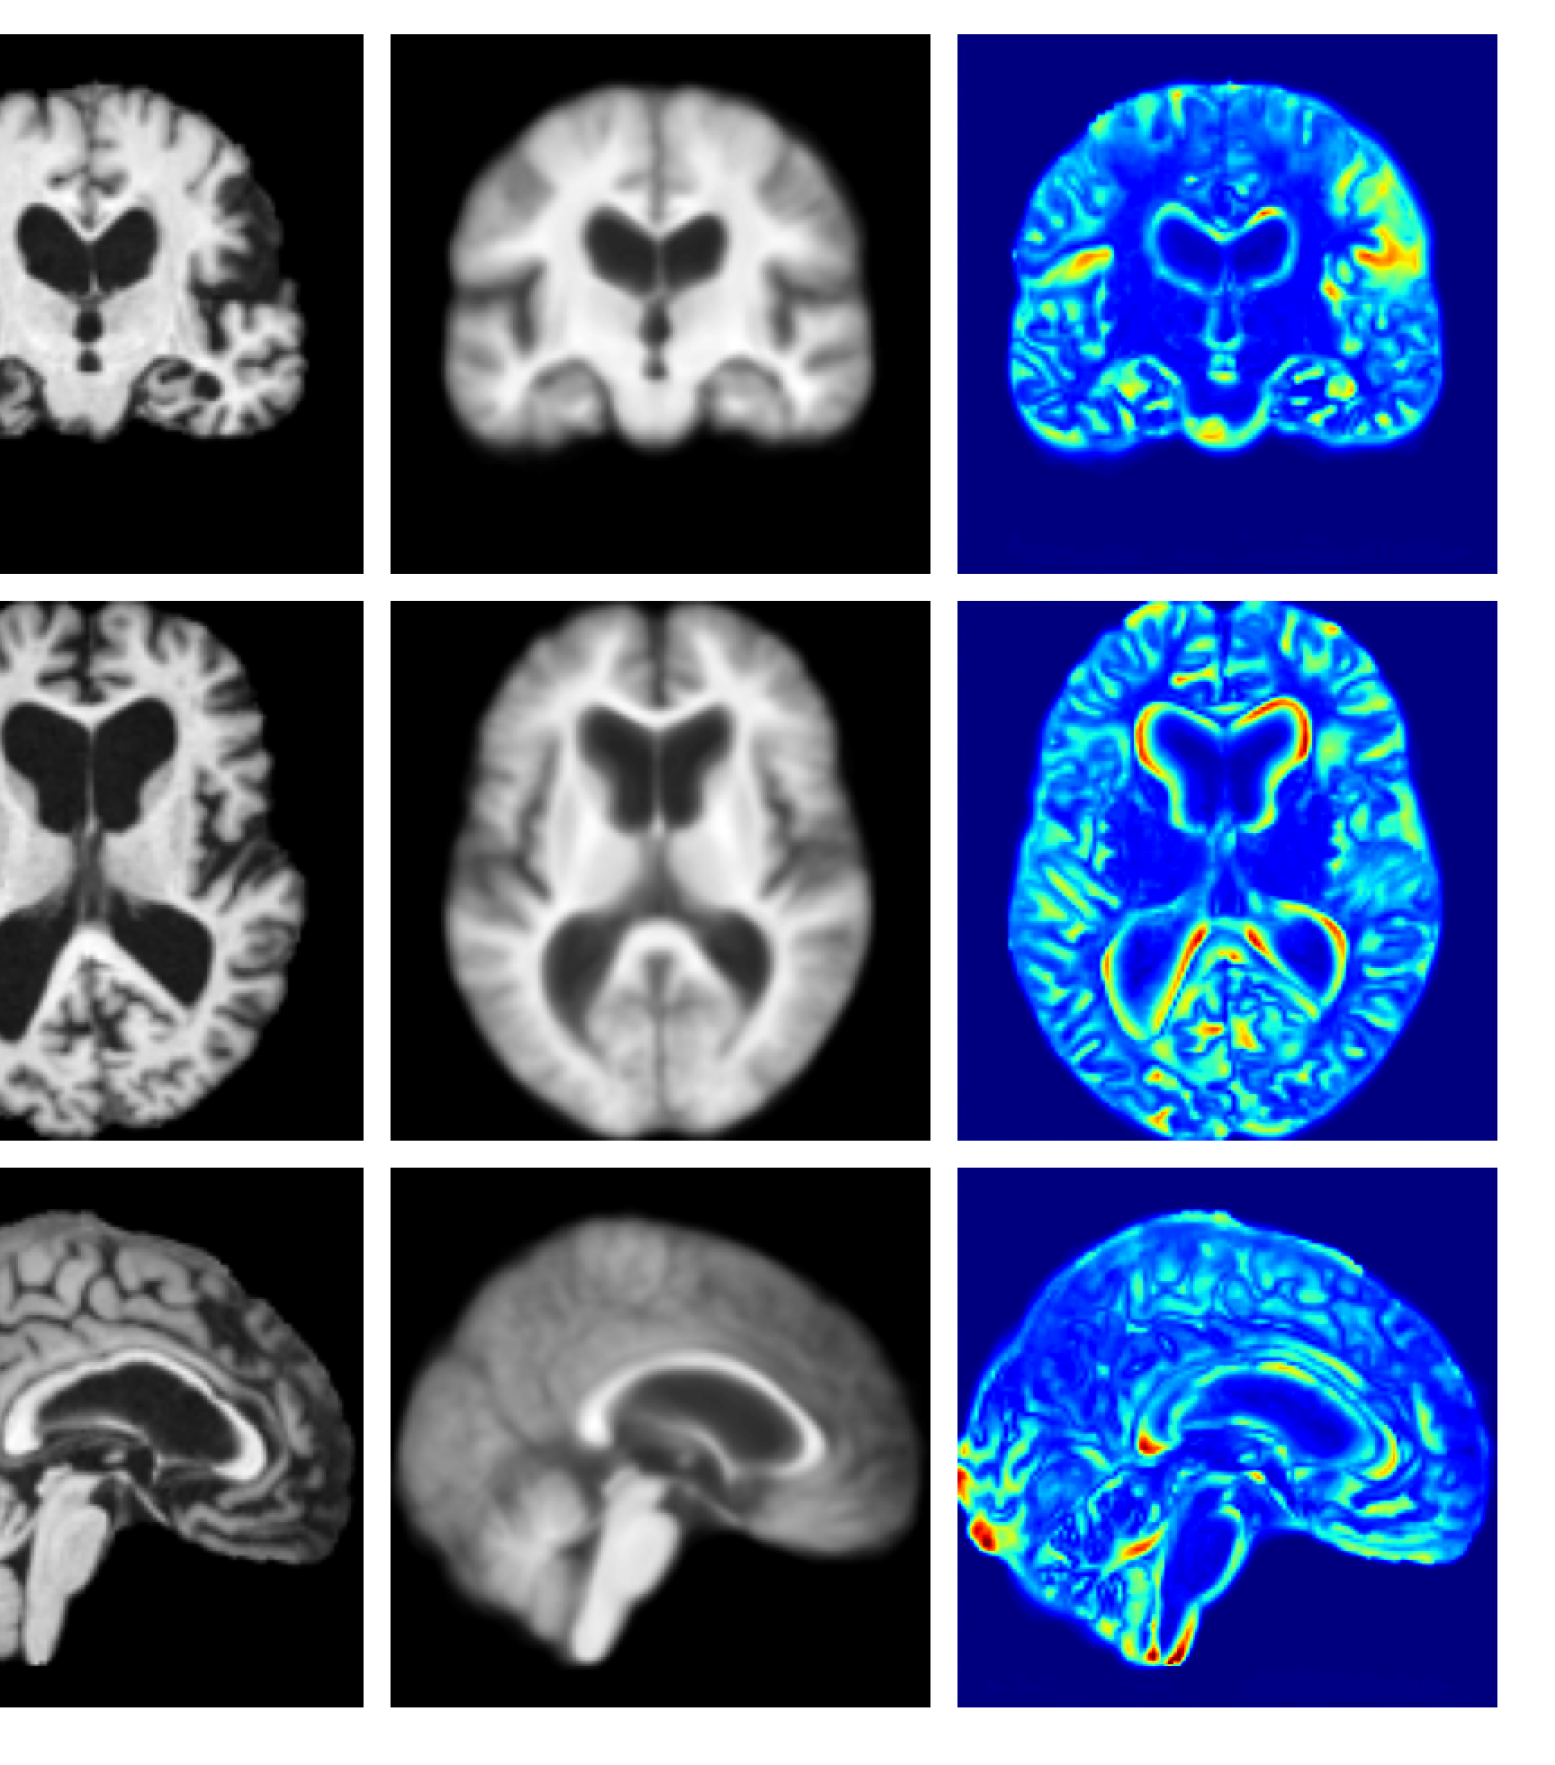

Figure 3: Example reconstructions and anomaly maps for a sample from the disease cohort of the UKBB dataset. Lesion and WMH are indicated in the original image by the red and yellow boxes respectively.

Figures 3 and 4, show example reconstructions and abnormality maps for a sample from the UKBB and UoTH datasets, respectively. Enlarged figures and additional example qualitative results for the ADNI dataset are available in the Supplementary. In Figure 3 we see that whilst all models are able to detect the lesion visible in the sagittal slice, the VAE, cVAE, LDM and LDM (TavgT_{avg}) produce very smooth outputs or lose defining characteristics and thus exhibit more false positives in healthy tissue. THOR and CADD provide the best results, with CADD better detecting white matter hypointensities (WMH). However, neither method fully inpaints all WMH, potentially due to presence of WMH in the healthy training set.

Figure 7 provides example reconstructions and anomaly maps for a healthy subject from the UK Biobank holdout test cohort.

Figure 7: Example healthy reconstructions and anomaly maps for a sample from the UK Biobank healthy test cohort. For a healthy subject, we should observe no regions highlighted in the anomaly map.